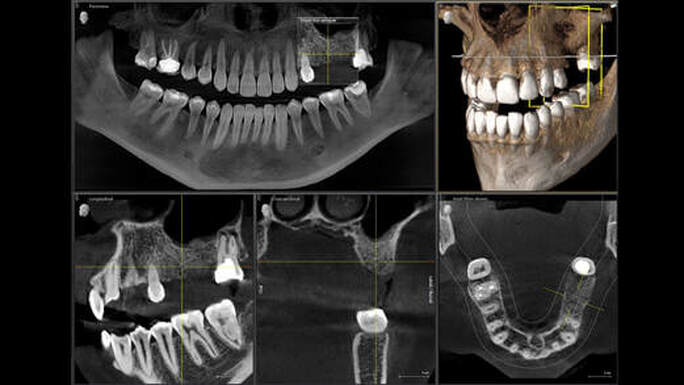

CBCT (Cone Beam Computed Tomography)

The CBCT a specialized medical imaging technique that created detailed 3D images of the oral and maxillofacial area. Unlike traditional 2D x-rays, CBCT provides a comprehensive view of the anatomy, including bone, teeth, nerves, and soft tissues, from multiple angles. This allows for precise diagnosis and treatment planning in various dental procedures.